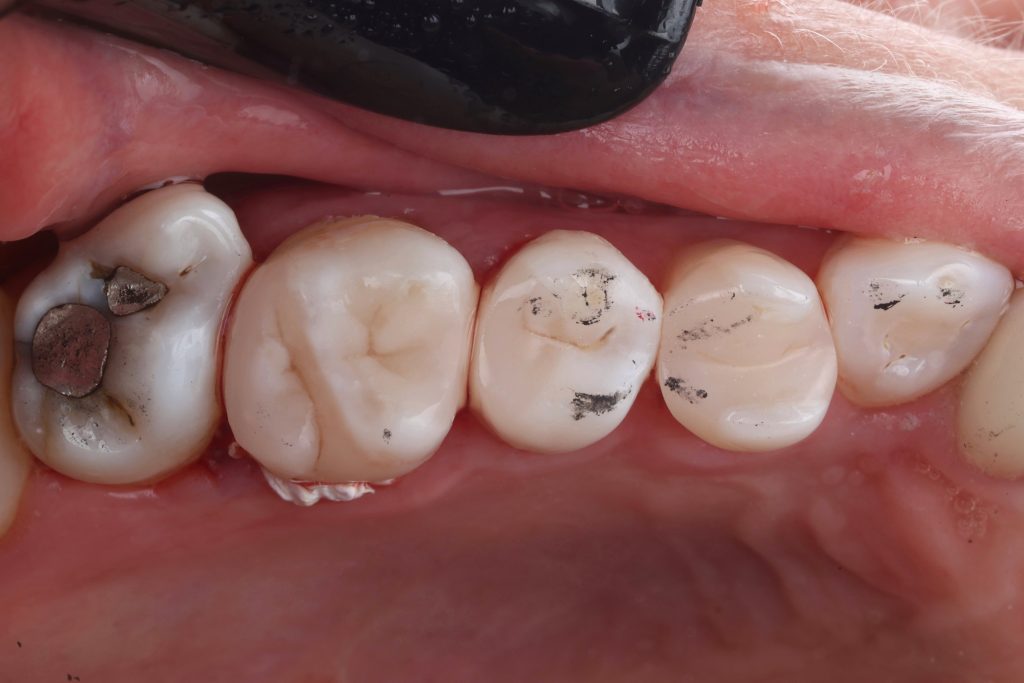

The initial situation is showing old defective composite restorations related to upper second premolar and first molar .

patient complained of pain & discomfort.

vitality test with Endo ice was checked and the results was positive .

Preoperative occlusal check done using 40 microns articulating paper. This is very important step to ensure a functional & esthetic anatomy avoiding high spots.